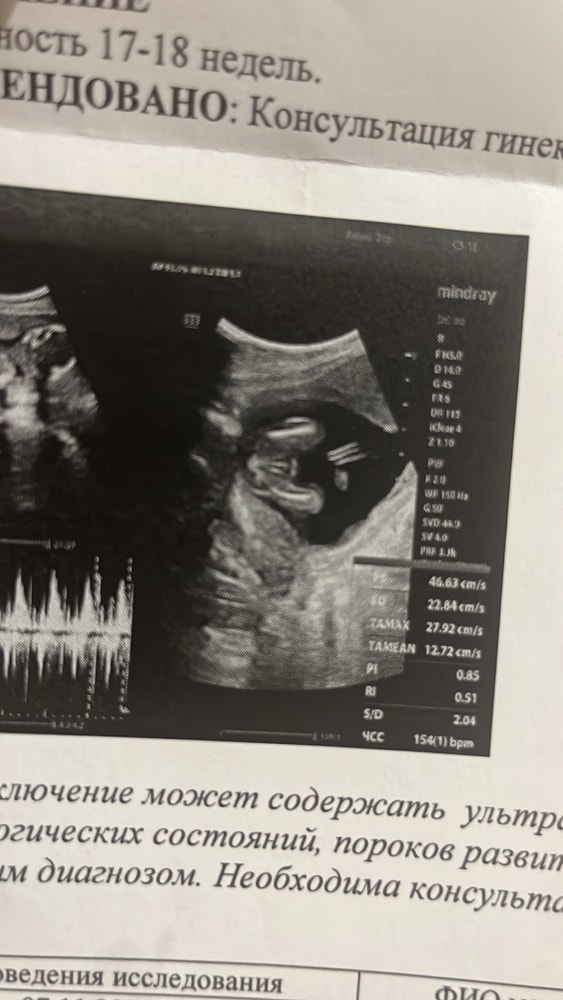

16-17 недель узи не могу понять мальчик или девочка

Была на узи в платном .Чисто на отвали посмотрели и дали конверт на руки .Снимок тоже не разборчив .Может вы увидите по снимке.Мальчик или девочка?

Жужу, вот такой листок дали .2 снимка вот есть .Не могу вообще понять где писюн или где пирожочек🙄😅

Ирина, у меня просто после двух пацанов ,даже не знаю .Не могу увидеть писюн .УЗИ было на 16-17 неделе беременности 😅